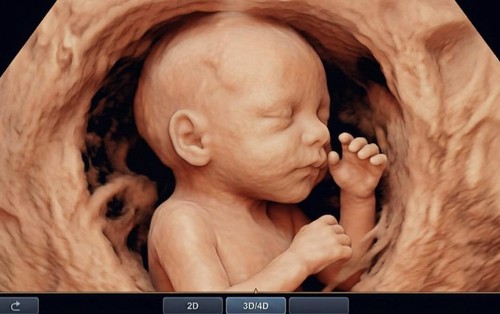

• Sản phụ khoa